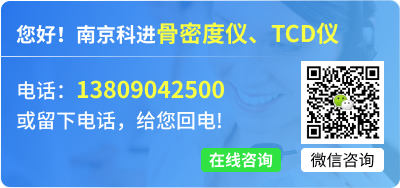

一、跟骨密度儀檢測時,耦合劑的涂抹位置

在受檢者的足跟上涂抹耦合劑時,是為了除去油囊和受檢者的足跟之間殘留的空氣,在足跟上涂抹充分的耦合劑,確保受檢部位與油囊接觸部位完全被覆蓋。

正確超聲耦合劑充分用量及位置